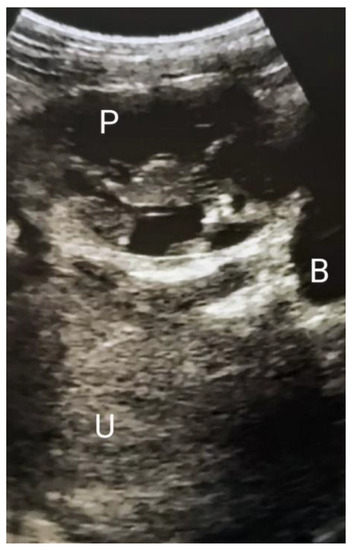

3. Case Presentation